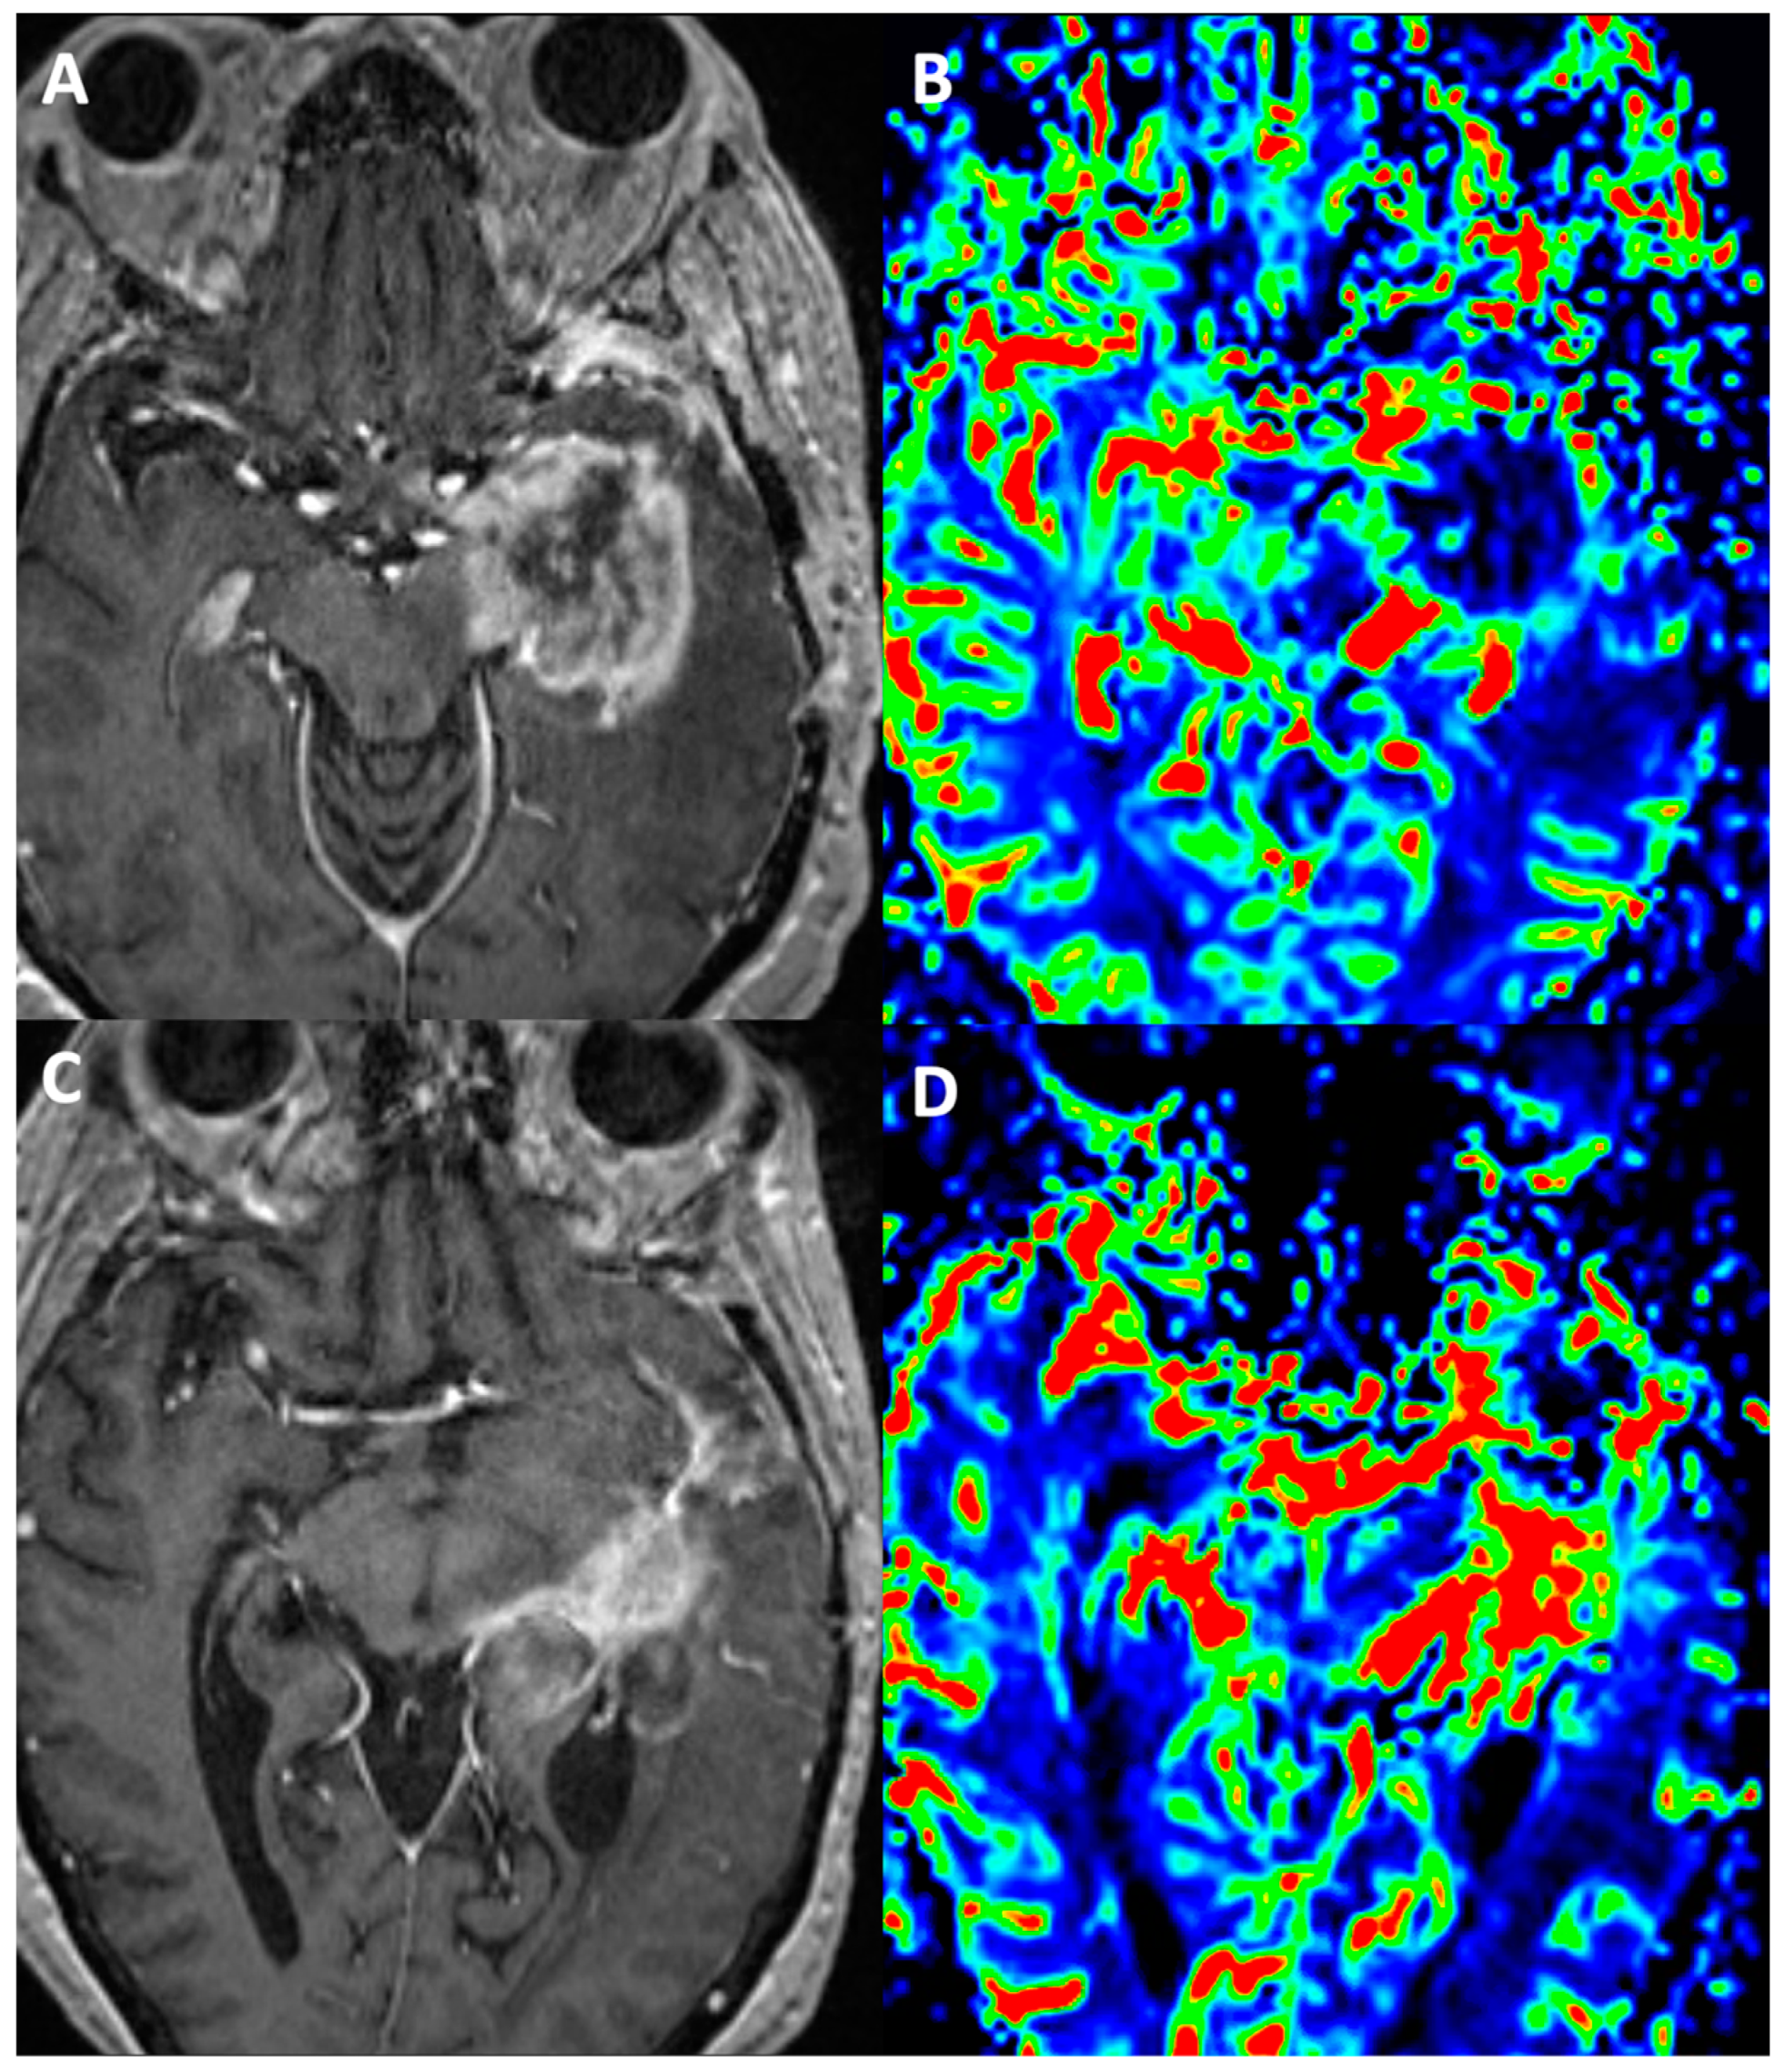

- Wang, L.; Wei, L.; Wang, J.; Li, N.; Gao, Y.; Ma, H.; Qu, X.; Zhang, M. Evaluation of perfusion MRI value for tumor progression assessment after glioma radiotherapy: A systematic review and meta-analysis. Medicine 2020, 99, e23766. [Google Scholar] [CrossRef]

- Pons-Escoda, A.; Smits, M. Dynamic-susceptibility-contrast perfusion-weighted-imaging (DSC-PWI) in brain tumors: A brief up-to-date overview for clinical neuroradiologists. Eur. Radiol. 2023. [Google Scholar] [CrossRef]